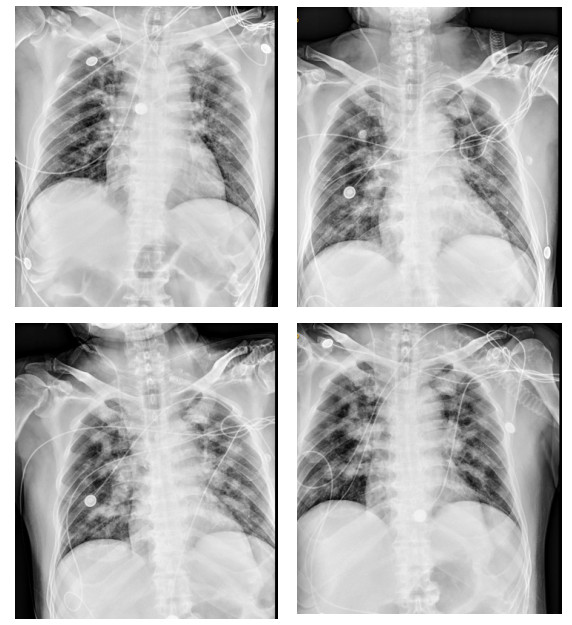

转入ICU后查体:神志模糊,躁动不安,偶有抽搐发作,呼吸急促,双肺可及湿罗音,立即予以气管插管接呼吸机辅助通气,镇痛镇静,头孢哌酮舒巴坦抗感染,继续予以利巴韦林抗病毒、免疫球蛋白应用以及保护脏器功能等对症治疗。2022-05-22患者布尼亚病毒核酸结果提示4.6×106 copies/mL,布尼亚抗体IgM阳性,相关化验提示:白细胞4.4×109/L,中性粒细胞绝对值3.03×109/L,血红蛋白141 g/L,血小板52×109/L,肌酐190 μmol/L,动脉血气pH 7.264,PO2 51.2 mmHg(1 mmHg=0.133 kPa),BE -8.3 mmol/L。床边胸片提示双肺炎症(见图 1),呼吸机支持参数较高,2022-05-23行床边气管镜检查(见图 2),气管内可见大量灰白色浓稠痰液,可见拉丝,予以充分抽吸并送检肺泡灌洗液,送检血G试验600 pg/mL,GM试验1.01 pg/mL,考虑重症肺炎,真菌感染可能,美国西弗吉尼亚大学医院深部真菌感染危险因素评分31分,予以调整抗感染方案为美罗培南联合伏立康唑抗感染治疗。2022-05-24患者肌酐持续升高,无尿伴代谢性酸中毒,予以行床边CRRT治疗。2022-05-27患者痰培养及肺泡灌洗液提示焦曲霉,进行CT检查,提示双肺异常密度(见图 3),予以调整抗感染治疗方案为头孢哌酮舒巴坦、伏立康唑、卡泊芬净抗感染治疗。经治疗后患者氧和指数稍好转,血小板计数较前升高(见图 4),2022-05-31患者家属因经济问题要求出院,1月后随访患者死亡。本研究通过医院伦理委员会批准(审批号:YX2022-041)。

图 1 患者2022-05-23、2022-05-24、2022-05-25、2022-05-29床边胸片